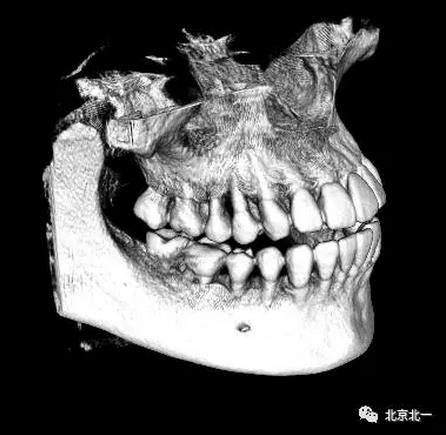

圖四:三維重建

圖五:三維重建可見牙冠突破舌側

圖九:重建后可見牙冠位于第二磨牙遠中,舌側傾斜。